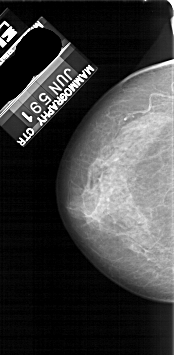

LEFT_CC LINES 4966 PIXELS_PER_LINE 2431 BITS_PER_PIXEL 12 RESOLUTION 43.5 NON_OVERLAY